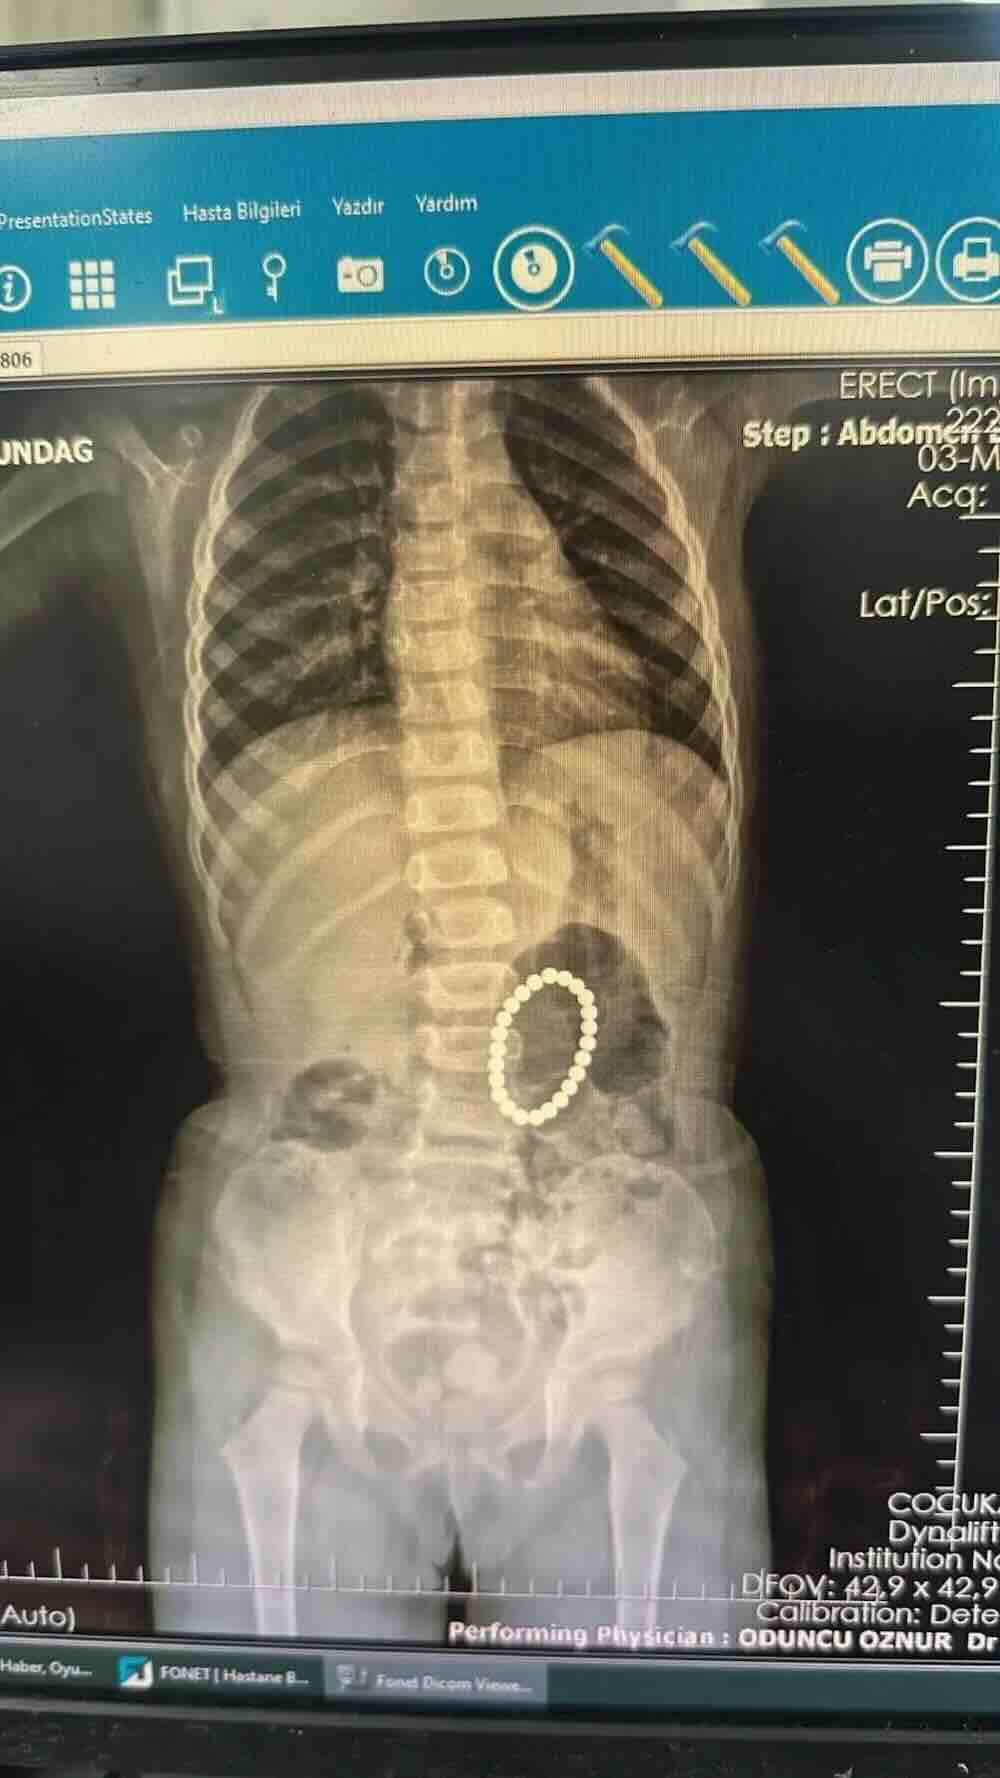

Basit gibi görünen bir şikâyetle başlayan süreç, sonunda herkesi şaşırtan bir tabloyu ortaya çıkardı. Şırnak’ta yaşayan 4 yaşındaki Rumeysa Altundağ, şiddetli karın ağrısı nedeniyle hastaneye götürüldü. İlk müdahalenin ardından Batman Eğitim ve Araştırma Hastanesi’ne sevk edilen küçük çocuk için yapılan ayrıntılı incelemeler, durumun tahmin edilenden çok daha ağır olduğunu gösterdi.

Endoskopi ve ameliyat sürecinde doktorlar da beklenmedik bir manzarayla karşılaştı. Rumeysa’nın mide ve bağırsaklarında çok sayıda yabancı cisim bulunduğu belirlendi. Yapılan değerlendirmelerde, bu maddelerin uzun süredir vücutta kaldığı anlaşıldı.

Çocuk Cerrahisi Uzmanı Dr. Selim Özkaya ve ekibinin gerçekleştirdiği operasyonla minik hastanın mide ve bağırsakları temizlendi. Ameliyat sırasında toplam 24 küçük mıknatıs çıkarıldı. Doktorlar, bu mıknatısların farklı zamanlarda yutulduğunu, bağırsak içinde birbirine tutunarak bazı bölgelerde delinmelere neden olduğunu ifade etti. Hasar gören alanlar da operasyon sırasında onarıldı.

Uzmanlar, çıkarılan mıknatısların paslanmış ve renk değiştirmiş olmasına bakarak, bu cisimlerin yaklaşık bir yıldır çocuğun vücudunda bulunduğunu değerlendirdi. Bu süre boyunca zaman zaman karın ağrısı yaşandığı, ancak olayın boyutunun fark edilmediği belirtildi.